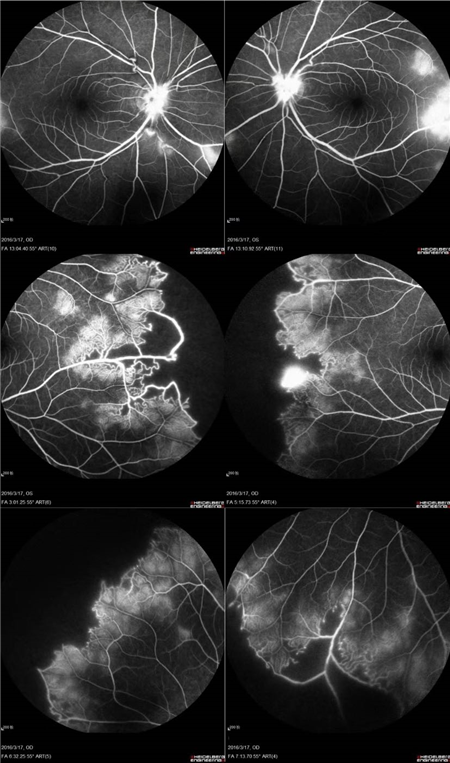

特发性视网膜血管炎、动脉瘤和视神经视网膜炎综合征(Idiopathic Retinal Vasculitis, Aneurysm, and Neuroretinitis syndrome,简称IRVAN综合征)是一种病因不明的较为少见的视网膜血管炎性疾病,此病症常在30-40岁发病且多为女性发病。在发病的前期,如果进行及时有效的治疗干预,预后效果多数较好。但一拖再拖,错过最好的治疗时间,可引起严重的并发症。在这里提醒大家,一定要密切关注自己眼部突发情况的出现,警惕眼前突然发生黑影飘动,视力下降的情况,尽早就医。

经过详细的眼底检查后,患者被诊断为IRVAN综合征引起的右眼黄斑裂孔,张风院长带领医生团队为患者施局右眼玻璃体切除+剥膜+眼内光凝+气液交换手术,经过半个月的恢复,患者右眼术后视力由术前0.3-达到0.6-的状态,且裂孔呈逐渐闭合状态。

视盘附近的动脉和动脉分叉处出现瘤样动脉扩张,视盘充血,边界不清,引起视盘周围视网膜内硬性渗出;视盘周可有少量放射状出血。

静脉不规则扩张和血管鞘膜,周边部小血管广泛闭塞,交界处毛细血管扩张和异常吻合。

严重者可发生从周边到黄斑的血管闭塞和缺血、玻血、新生血管性青光眼,最终视神经萎缩。

长期追踪发现动脉瘤是一种血管炎性的游走性改变,炎症消失时,血管壁强度恢复,瘤体减小,甚至恢复正常。